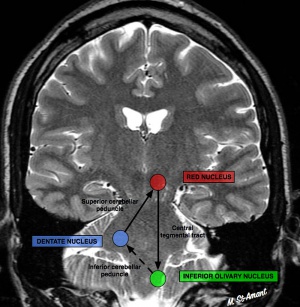

OPT is a delayed complication of a brainstem lesion affecting the dentato-rubro-thalamic tract, also known as the Guillain-Mollaret triangle (see diagram below). The tract originates in the cerebellar dentate nucleus and travels to the contralateral red nucleus in the central tegmentum of the midbrain. The tract continues to the ipsilateral inferior olivary nucleus via the central tegmental tract. Damage to or disruption of any part of this tract results in secondary inferior olivary nucleus hypertrophy (IONH), forming the pacemaker of the aberrant signaling that results in OPT. Damage to the dentate nucleus results in contralateral IONH, while damage to the central tegmental tract results in ipsilateral IONH. Although IONH does not necessarily result in the occurrence of OPT, the presence of OPT always requires IONH. It should be noted that hypertrophy is a misnomer, as this phenomenon is due to pseudohypertrophy.